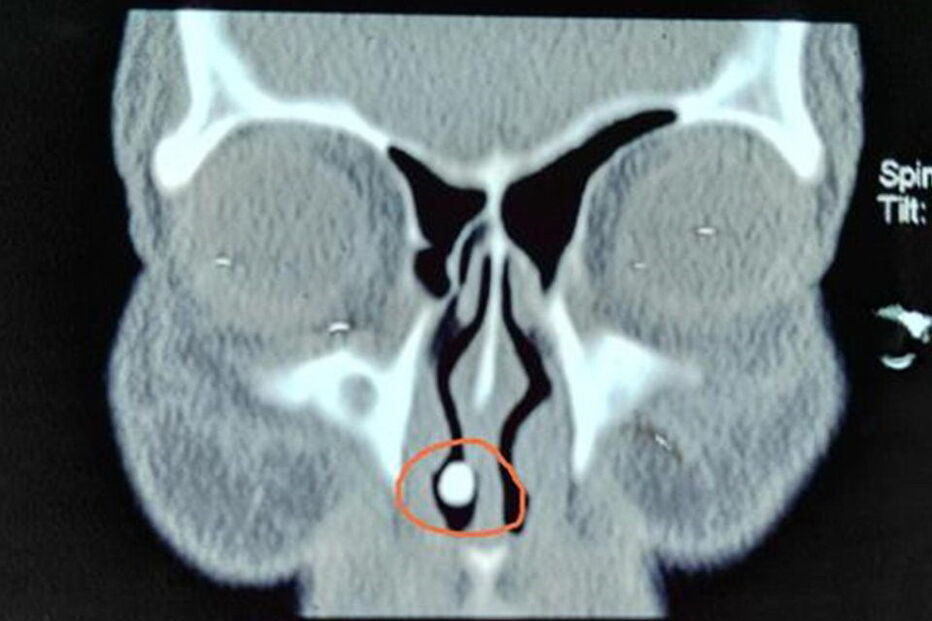

Os médicos estranharam as hemorragias constantes e que duravam há cerca de 50 anos e resolveram fazer a tomografia. O exame revelou uma "massa de alta densidade na cavidade nasal direita".

"Pensamos que fosse um objeto que ali tinha sido introduzido, ou uma pedra que ela em criança tivesse posto ali e ficado alojada", contam os médicos. Mas a cirurgia revelou um achado bem mais insólito: tratava-se de um dente que tinha nascido no nariz da paciente. Estava completo, tinha coroa e raiz.